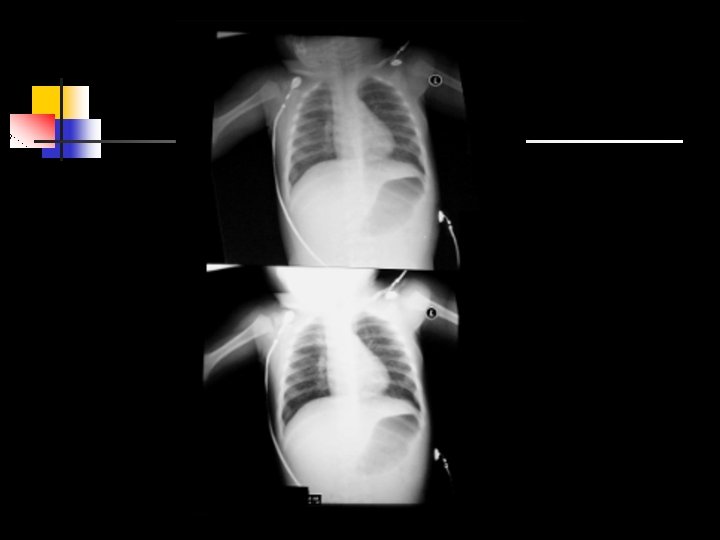

80 kvp 200 mas 10 mas 80 kvp Note Quantum Mottle 84

Dose Implications 1. 2. Images nearly always look better at higher exposures. Huge dynamic range means nearly impossible to overexpose. 85